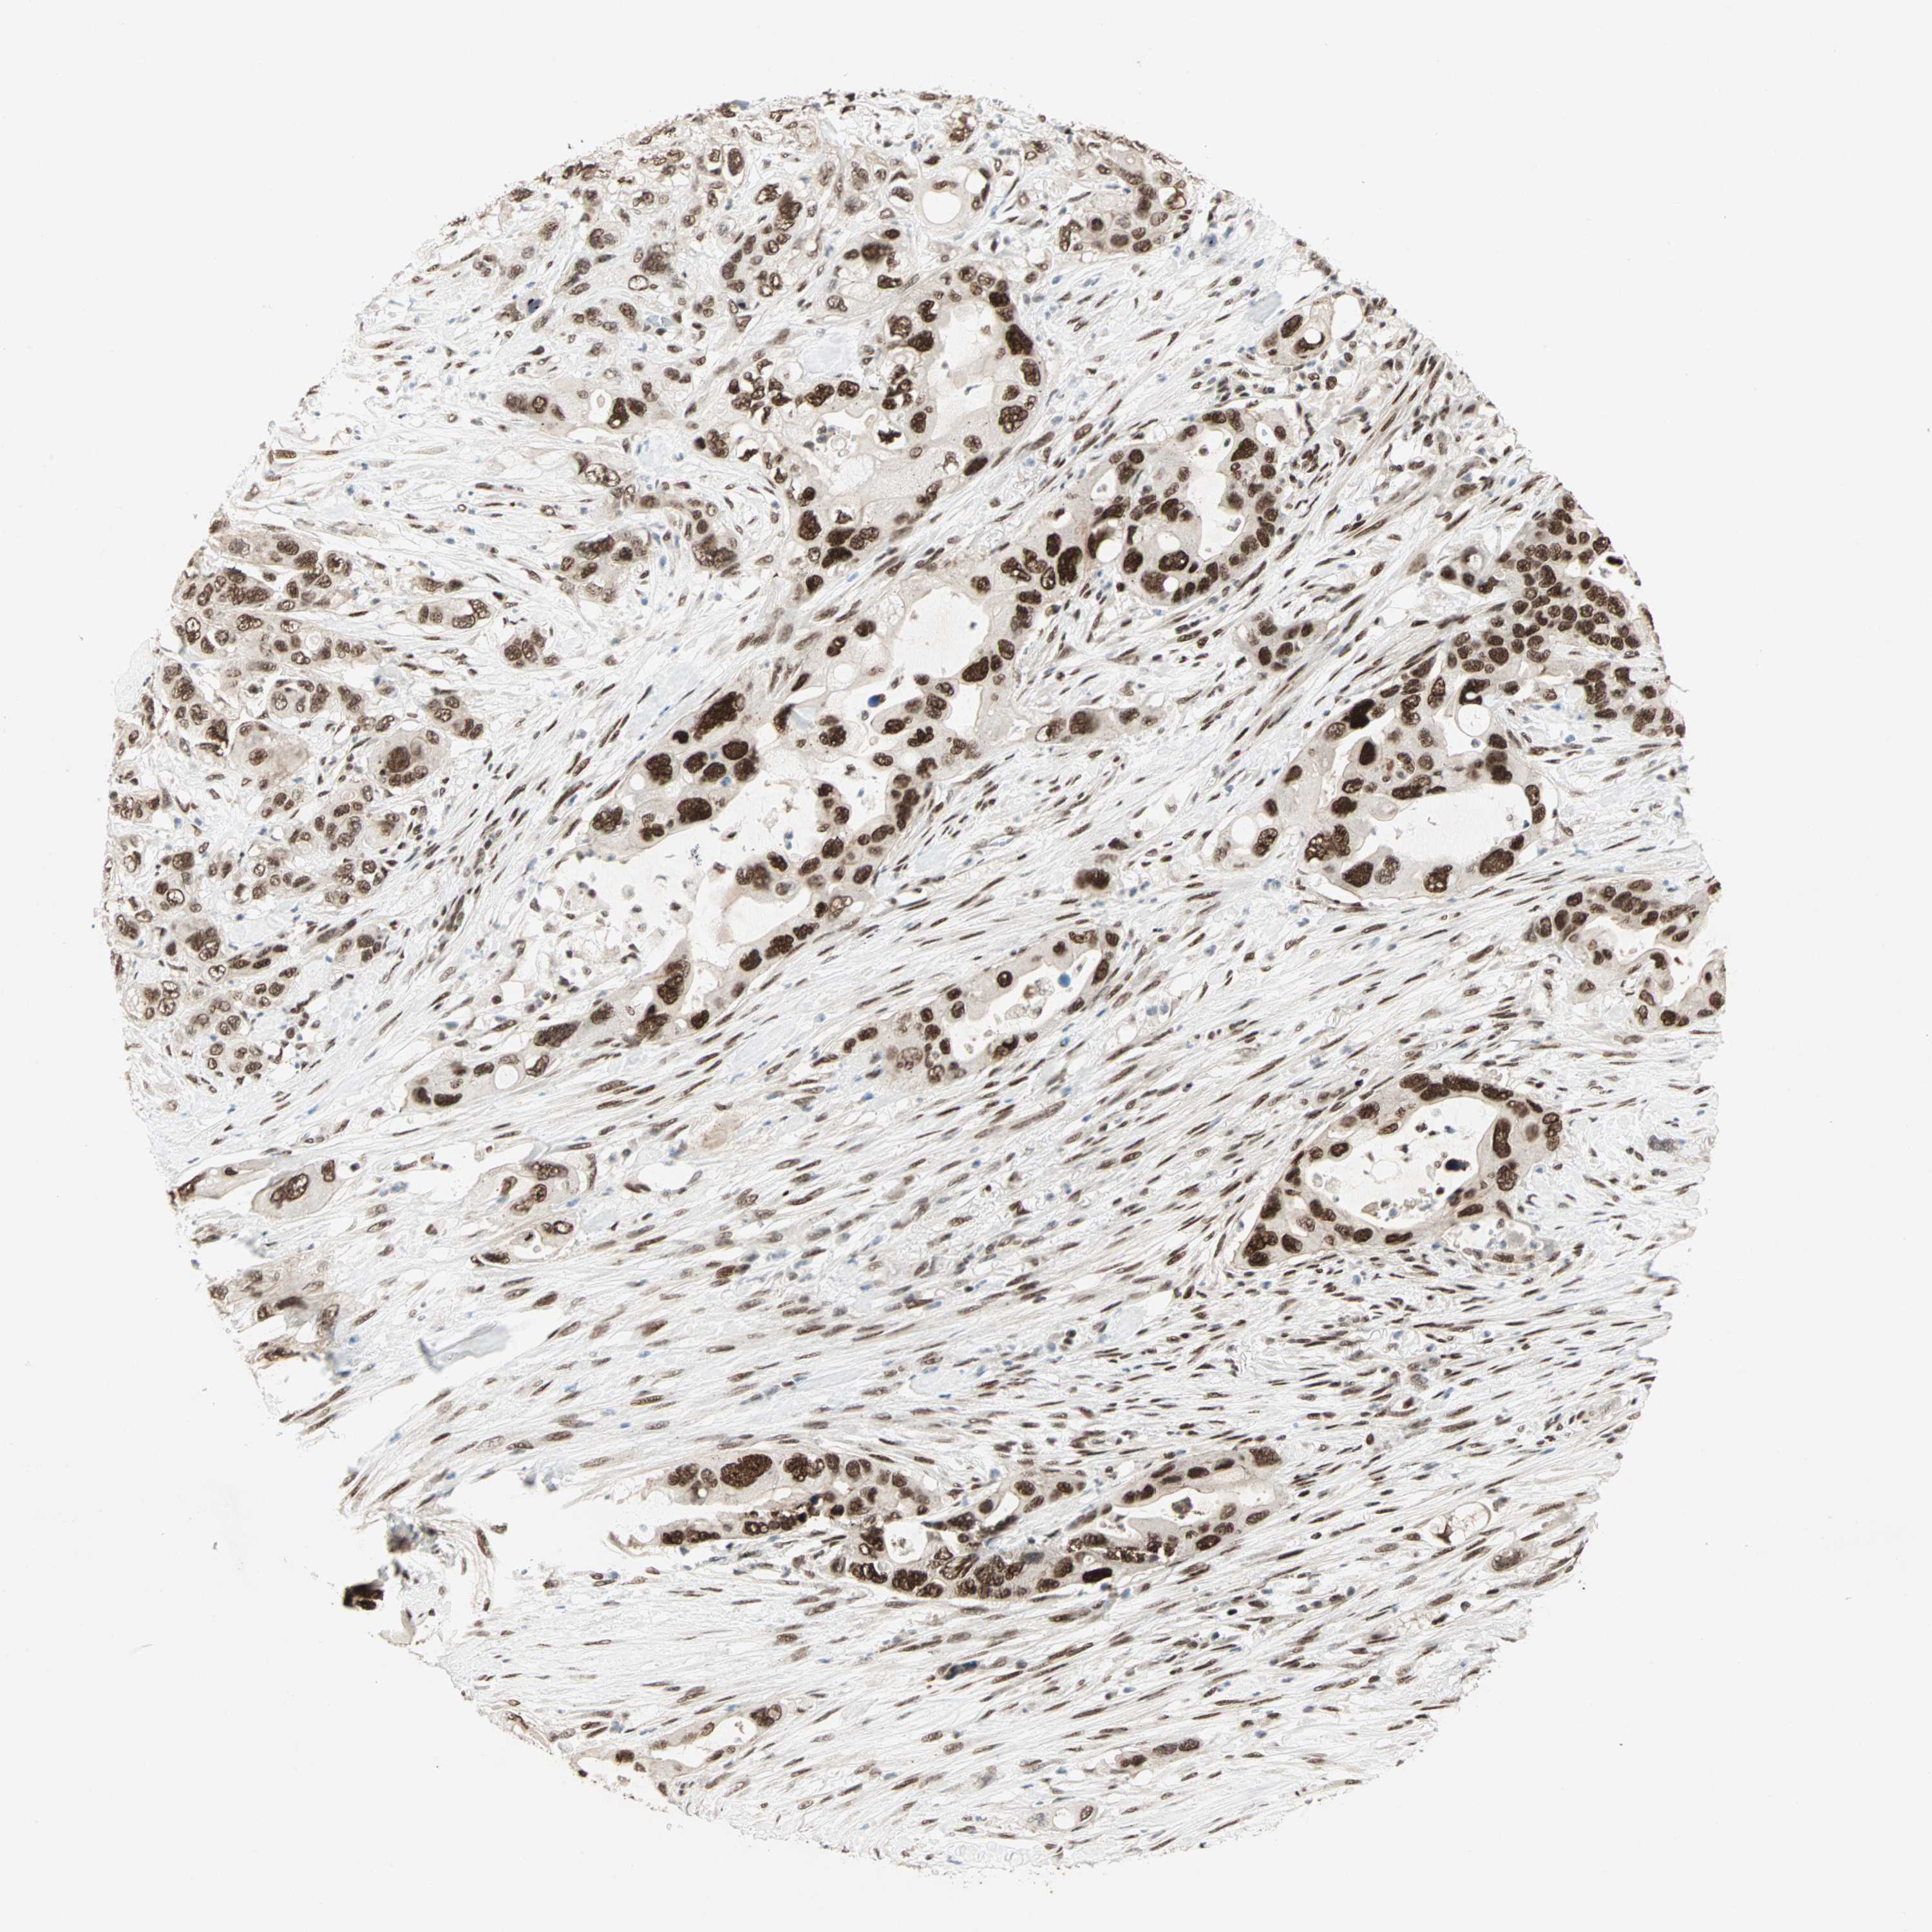

PANCREATIC CANCER - Protein expressioni

A mouse-over function shows sample information and annotation data. Click on an image to view it in a full screen mode. Samples can be filtered based on level of antibody staining by selecting one or several of the following categories: high, medium, low and not detected. The assay and annotation is described here.

Note that samples used for immunohistochemistry by the Human Protein Atlas do not correspond to samples in the TCGA dataset.

Antibody stainingi

Antibody staining in the annotated cell types in the current human tissue is reported as not detected, low, medium, or high, based on conventional immunohistochemistry profiling in selected tissues. This score is based on the combination of the staining intensity and fraction of stained cells.

Each image is clickable and will lead to virtual microscopy that enables deeper exploration of all samples and also displays staining intensity scores, fraction scores and subcellular localization as well as patient and tissue information for each sample.

Antibody HPA005689

Staining

High

Medium

Low

Not detected

Intensity

Strong

Moderate

Weak

Negative

Quantity

>75%

75%-25%

<25%

None

Location

Nuclear

Cytoplasmic/membranous

Cytoplasmic/membranous,nuclear

Adenocarcinoma, NOS

Adenocarcinoma, metastatic, NOS